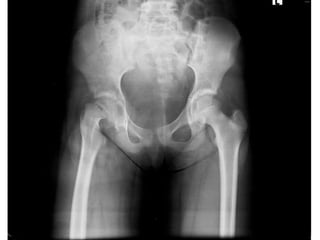

Investigation

•Film pelvis AP

•Film both hips AP

Diagnosis

• Slipped Capital Femoral Epiphysis Right Hip

Diagnosis • Slipped CapitalFemoral Epiphysis Right Hip